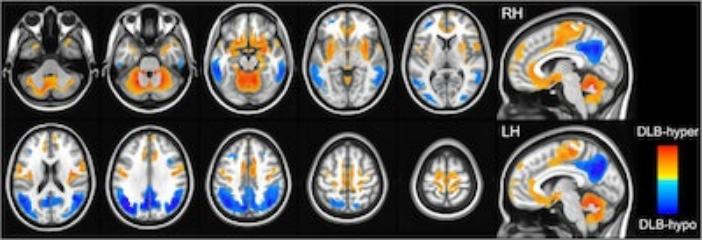

DLB-hypo (路易體癡呆的低代謝變化)的特點是雙側頂葉、顳葉和枕葉皮質的雙側代謝活動相對減少(顏色編碼為藍色),而DLB-hyper (路易體癡呆的高代謝變化)顯示小腦、雙側感覺運動、眶額、島葉和海馬旁皮質、雙側殼核、蒼白球、海馬和杏仁核的代謝活動相對增加(顏色編碼為紅色)。圖片由npj Parkinson’s Disease提供。

根據研究結果,DLB- hypo與語言、視覺空間、視覺記憶和額葉/執行功能有關,而DLB-hyper負責注意力和言語記憶。此外,他們寫道,線性混合模型顯示,無論認知狀態如何,DLB-hypo與縱向認知結果相關,DLB- hyper只導致輕度認知衰退患者的認知衰退。